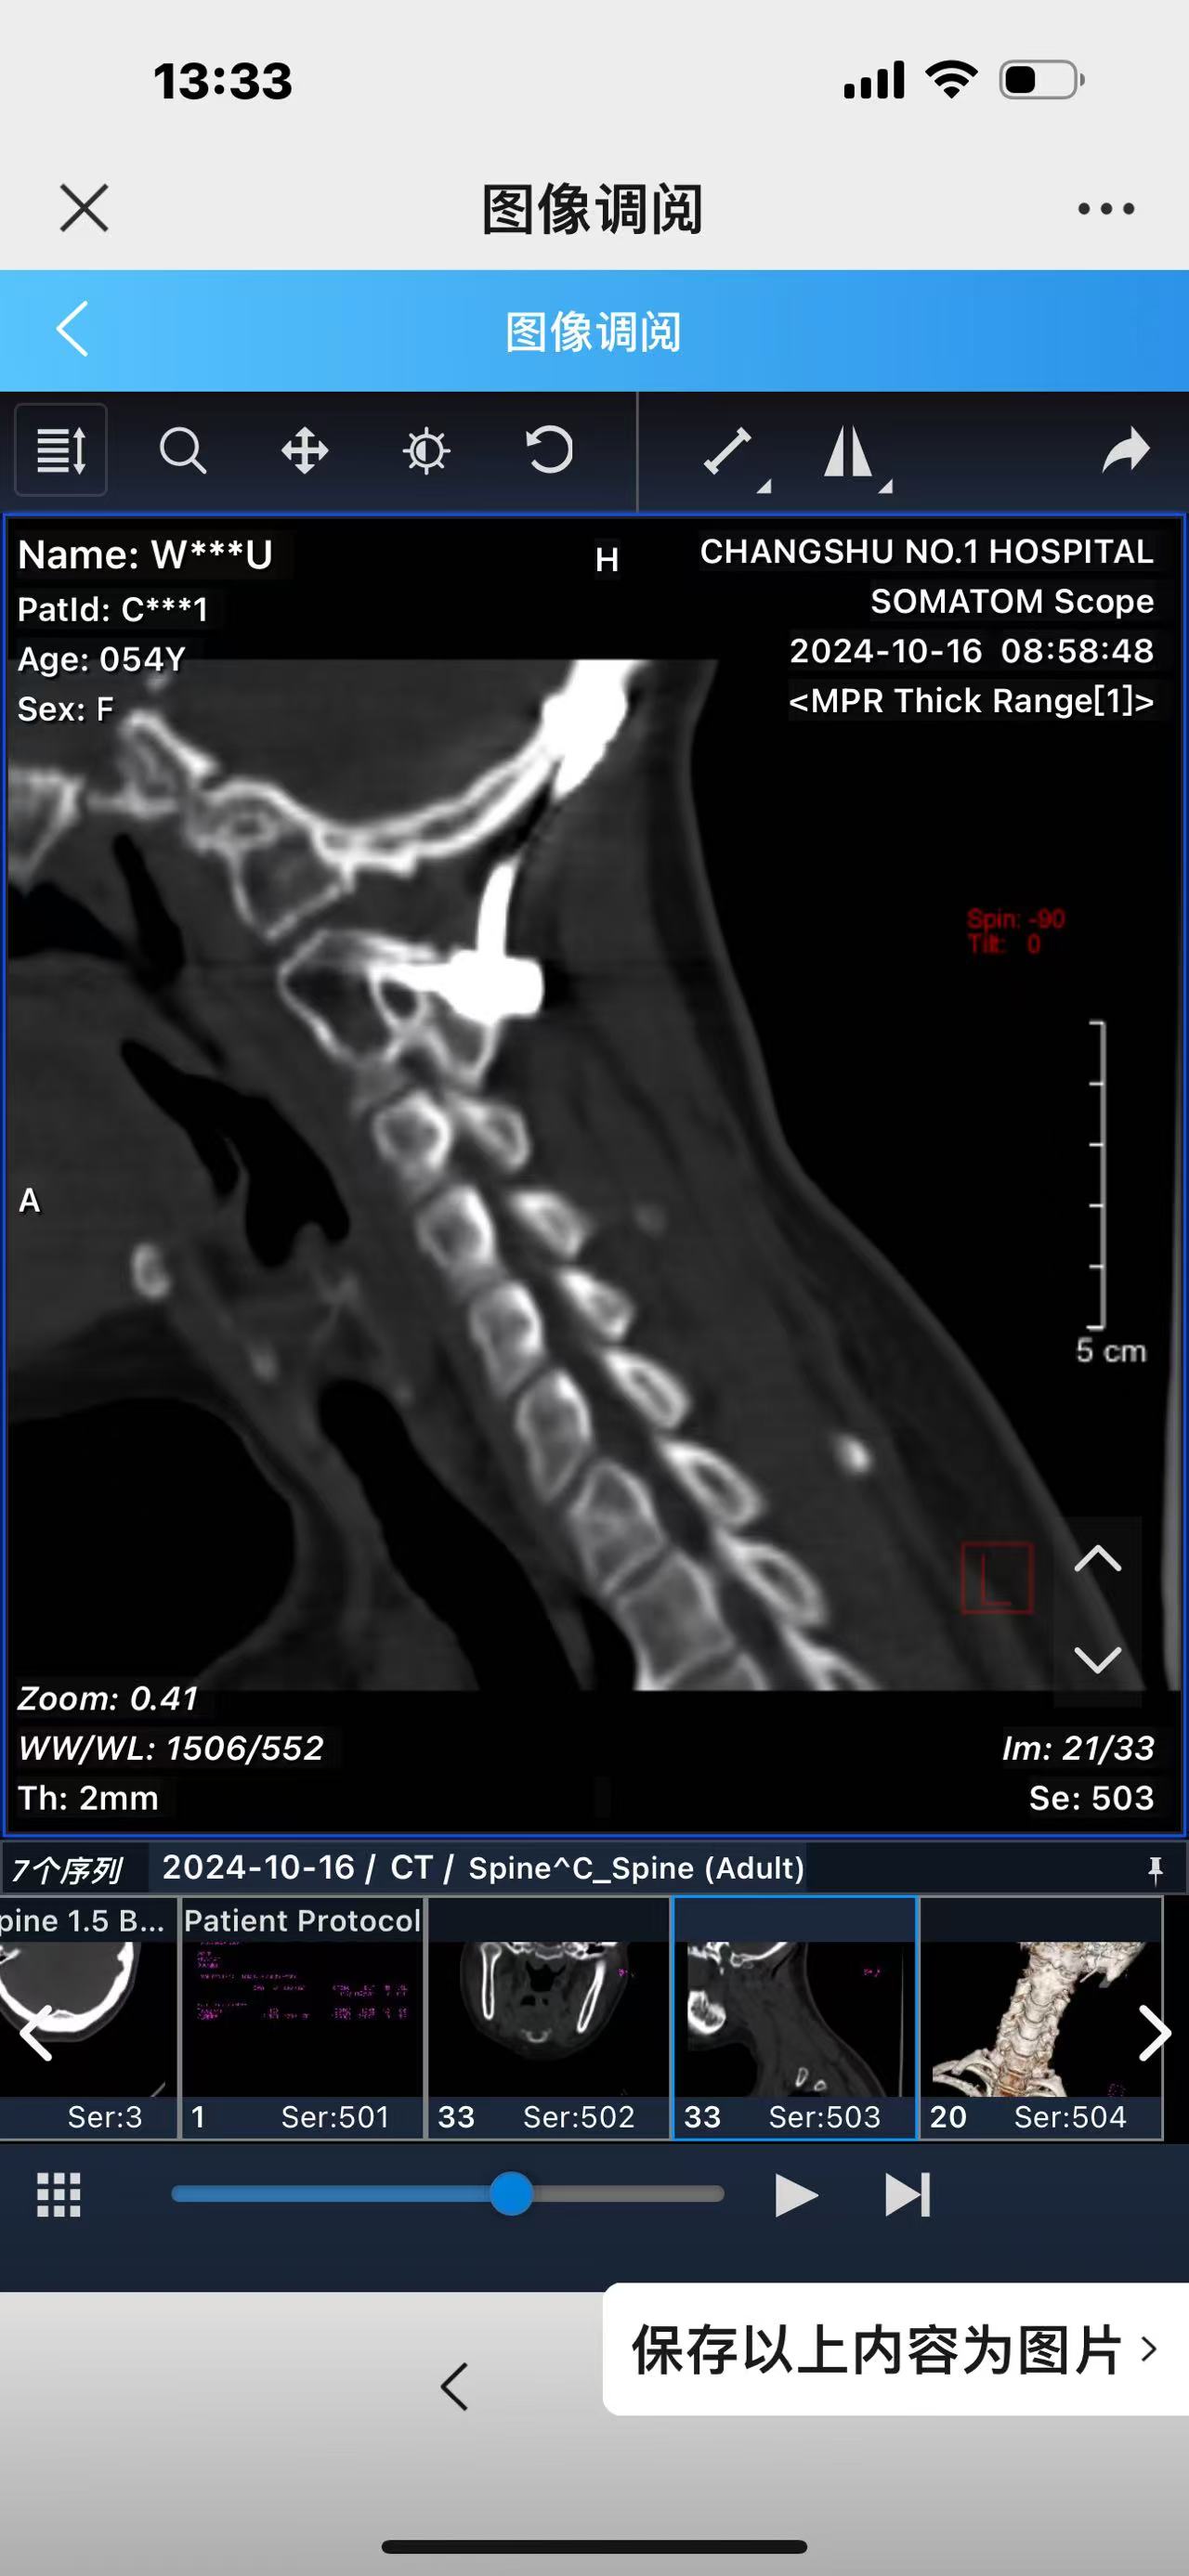

• 诊断:寰枢椎脱位,颅底凹陷

• 日期:2023.09

• 医院:北三医院

• 主刀:王超

• 术后影像:

• 2024.02.27,复查,对位良好,偶尔会肩甲骨酸,坐下就不酸。

• 2024.10.20,复查,对位良好,偶尔会肩甲骨酸,坐下就不酸。